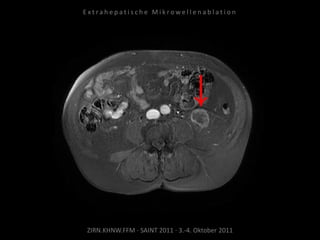

Kontrolle:

MRT 18.05.2010

MRT 01.07.2010

Das abladierte Tumorrezidiv zeigt keine

Vitalität. Jedoch neu aufgetretene

Tumormanifestation kranial im Bereich der

angrenzenden Samenbläschen.

Ablation des entsprechenden Areals

am 06.07.2010:

2 Nadelpositionen.

Erneut mit Kühlung von Harnleiter,

Harnblase und Rektum.